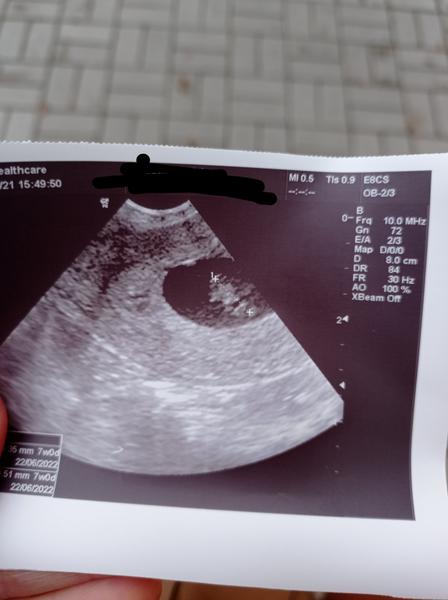

@jajajungmannova Snad to bude v poradku, pro porovnani, toto je moje v 7+4 (1 cm velke embryo, tj spis 7 +0).